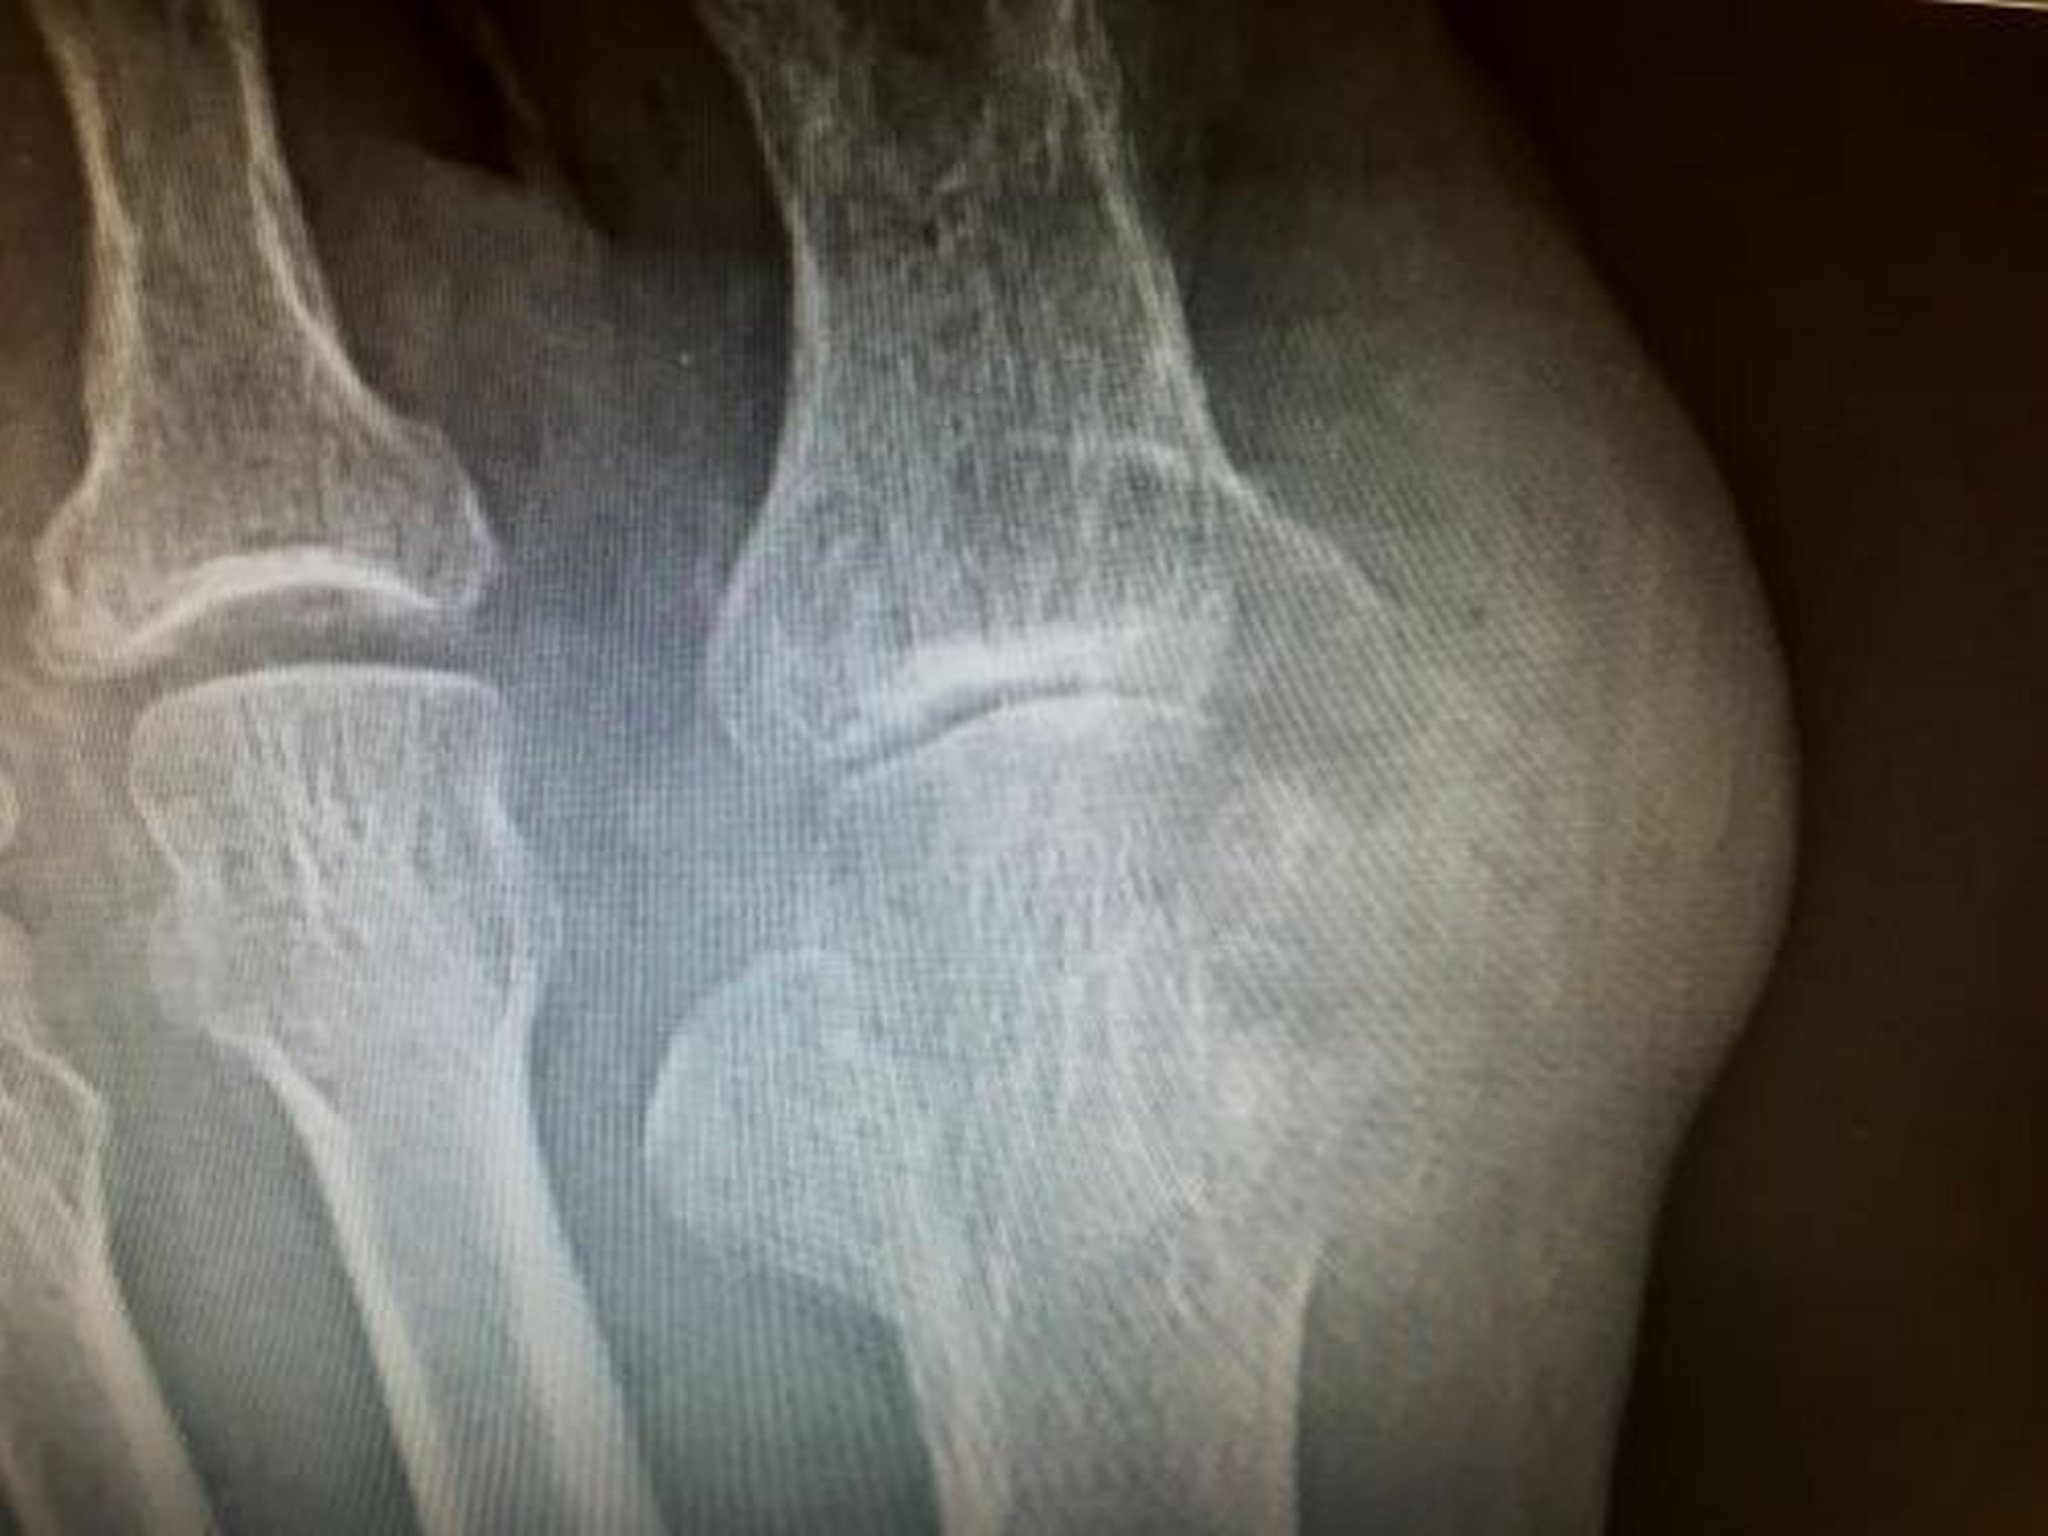

I reperti del liquido sinoviale da versamenti cronici delle articolazioni colpite sono di solito diagnostici. Le radiografie dell'articolazione colpita non sono necessarie se la diagnosi di gotta acuta è stata posta con l'analisi del liquido sinoviale e raramente mostrano erosioni al momento dei primi attacchi.

L'artrite gottosa cronica deve essere presa in considerazione nei pazienti con persistente malattia articolare inspiegabile o con tofi sottocutanei o ossei. Possono risultare utili RX della 1a articolazione metatarsofalangea o delle altre articolazioni colpite. Queste RX possono mostrare lesioni a stampo nell'osso subcondrale con margini ossei debordanti, soprattutto a livello della prima articolazione metatarsofalangea; le lesioni devono avere un diametro 5 mm per essere visibili alla RX. Lo spazio articolare è tipicamente conservato fino agli stadi tardivi della malattia.

L'ecografia diagnostica è sempre più utilizzata per rilevare un segno tipico di doppio contorno che suggerisce la deposizione di cristalli di urato, ma la sensibilità è operatore-dipendente e la differenziazione dal deposito di cristalli di pirofosfato di calcio può essere più difficile da fare in modo conclusivo. La deposizione di urati sulla cartilagine articolare (segno a doppio contorno) e tofi clinicamente non evidenti sono cambiamenti caratteristici. Questi risultati possono essere evidenti anche prima della prima crisi di gotta. La TC a doppia energia può anche rivelare depositi di acido urico e può essere utile se la diagnosi non è chiara in base alla valutazione clinica standard e ai test (7), in particolare se l'aspirazione e l'analisi del liquido sinoviale non possono essere eseguite. Nessuna modalità di imaging è completamente accurata, in particolare quando si valuta una prima riacutizzazione.